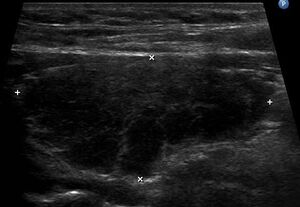

| The thyroid of someone with Hashimoto's thyroiditis as seen with a microscope at low magnification | |